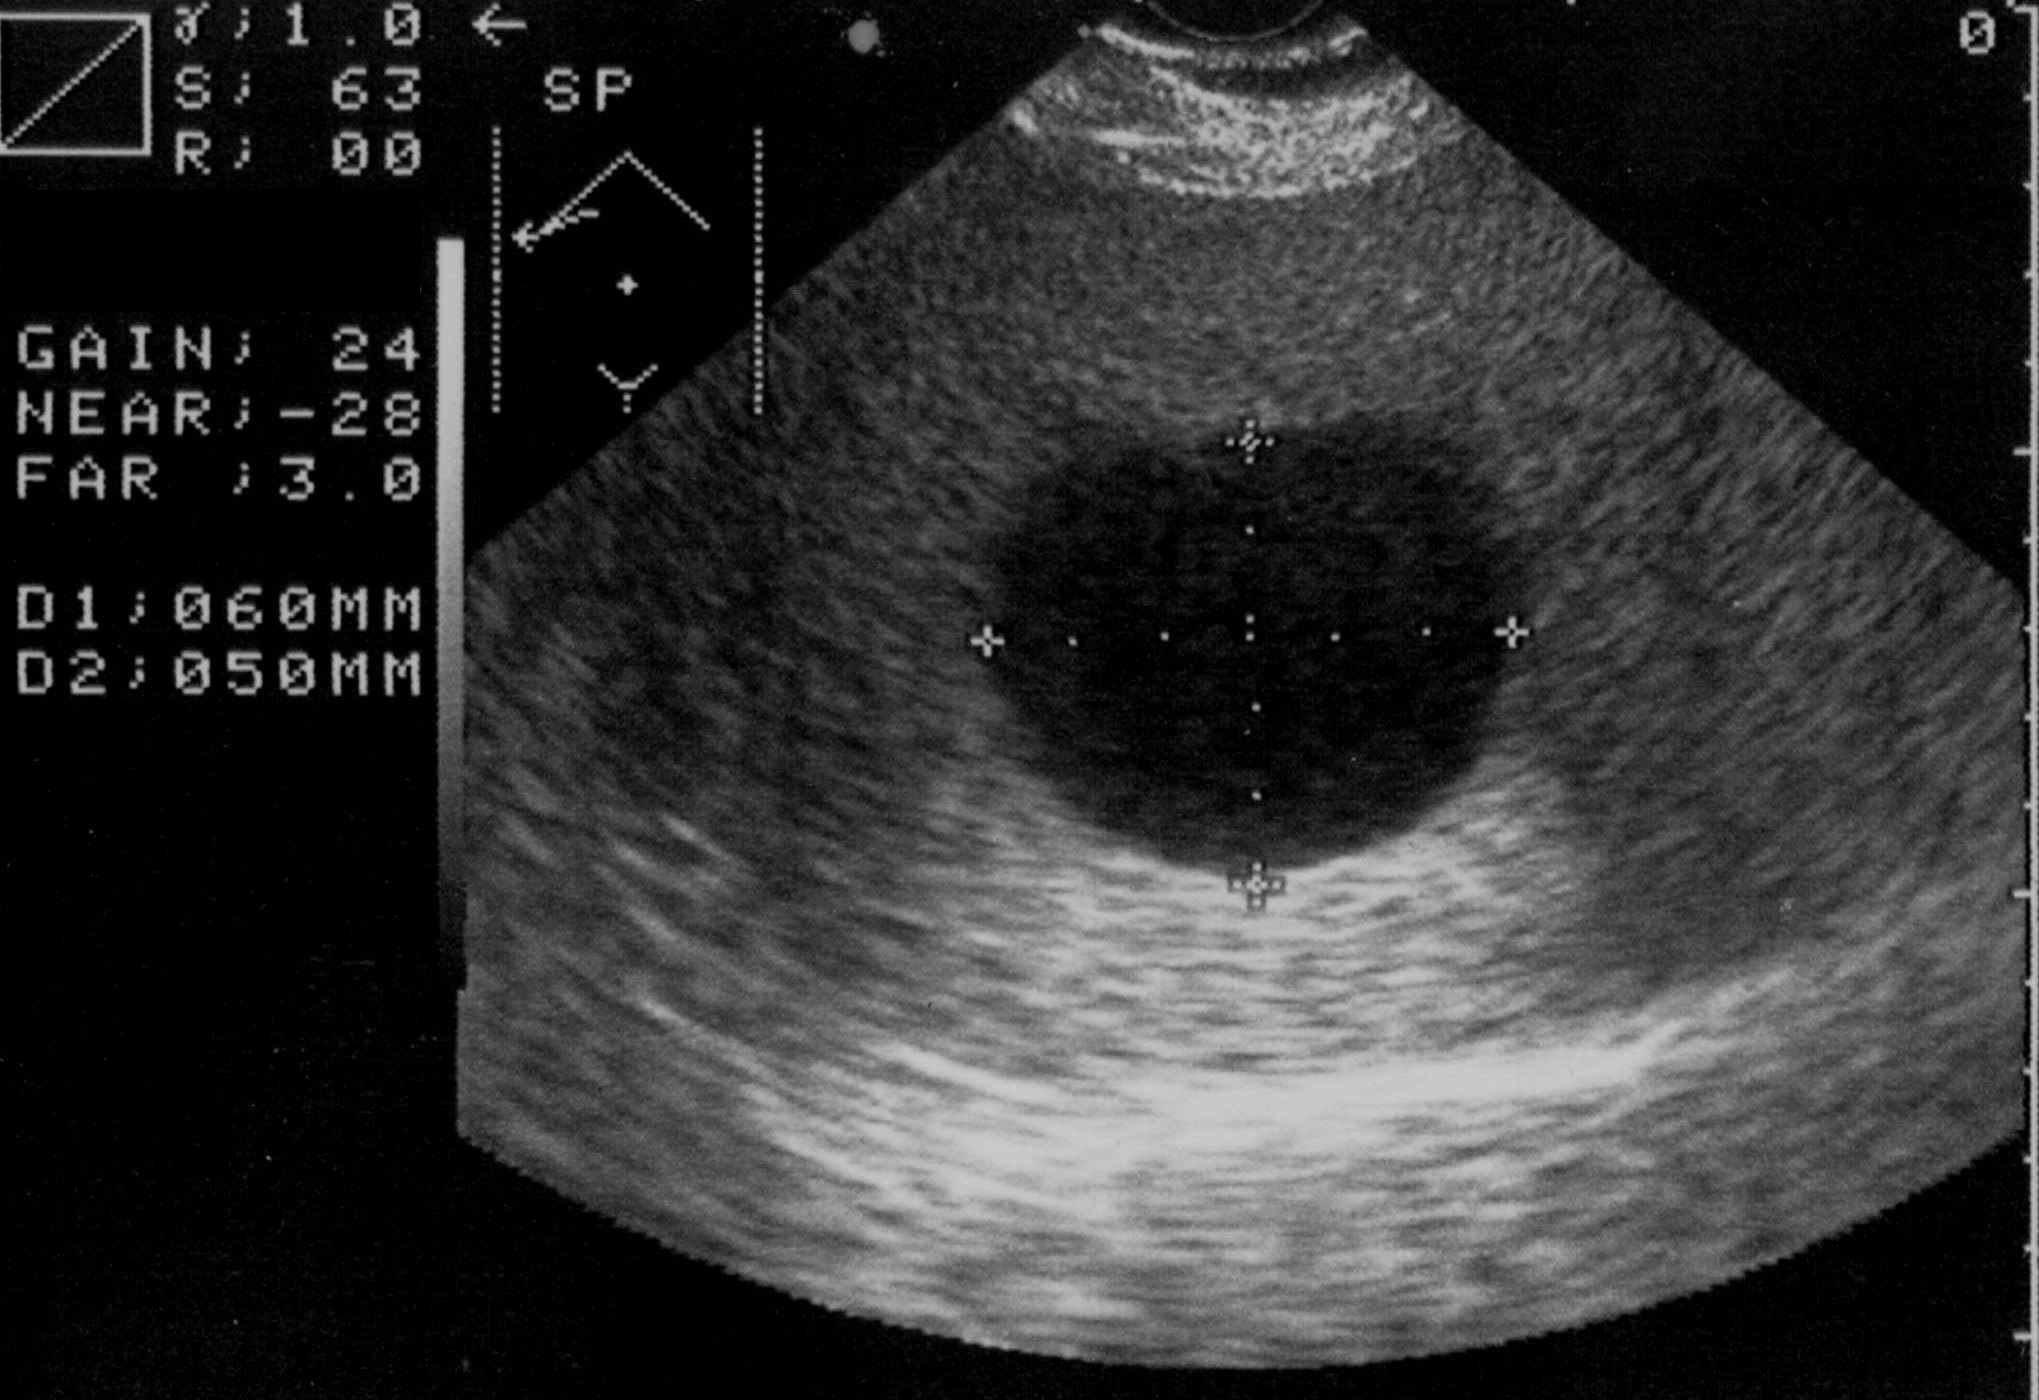

Very variable appearence forms can be observed by US and CT examinations from the early cyst in active phase to the cyst of the died parasite with a calcified wall (although the calcium appearing in the wall of the cyst does not mean that the parasite has unambiguously consumed) in case of an E. granulosus infection (Figure 15).

Figure 15: Echinococcus cyst in the liver, contrast enhanced CT

On the other hand, the liver parenchyma affected by E. multilocularis appears as areas with irregular contour and mixed echogenecity (US) or density (CT) including a hypoechoic (US) or hypodens (CT, this is already the necrotic area) necrotic center (multilocular cyst with inner matrix).